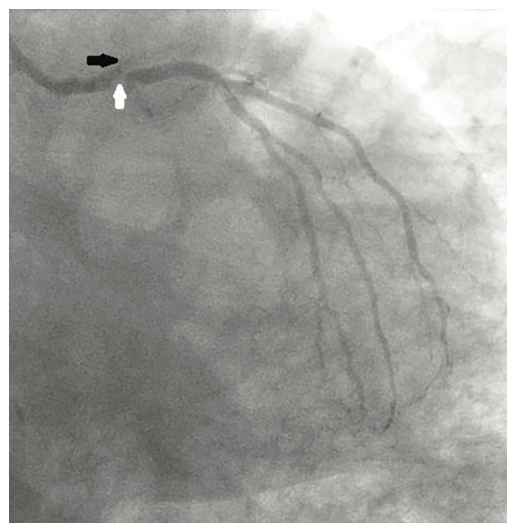

Following the Perclose placement, we upsized to a 14 Fr x 13 cm Cook Medical sheath (Figures 7-8), and through that, advanced a JR catheter into the ventricle and switched out for the Impella 2.5 device (Figure 9). A JR4 and eventually, an Amplatz right (AR) mod, was used from the right ulnar to engage the RCA, and an Extra Backup (EBU) 3.5, 7 Fr (Medtronic) was used from the groin. Dual angiography was performed (Figure 10). Once the activated clotting time (ACT) was >300 seconds, the ramus was wired with a Marvel wire (Boston Scientific). We attempted to cross the LAD CTO using a Corsair (Asahi Intecc) and a Pilot 200 (Abbott Vascular). The Pilot 200 crossed, but it appeared to be in the diagonal and could not be redirected down the LAD. A Gaia second (Asahi Intecc) was able to cross into the LAD (Figure 11), and at that point, was switched out via the Corsair for a workhorse wire, a Runthrough (Terumo). An 0.9 laser (Spectranetics) was used perform laser atherectomy for a minute and a half on the LAD (Figure 12), but we could not get the catheter across. However, this allowed us to advance a balloon across the lesion and we predilated with a 1.5 mm x 20 mm Mini Trek (Abbott Vascular) and then a 2.0 mm x 20 mm balloon. The same 2.0 mm x 20 mm balloon was used in the ramus. A 2.5 mm x 15 mm AngioSculpt (Philips) was used to predilate the LAD, but on its return, the AngioSculpt became stuck and would not come back. We got it partially into the guide and then the shaft broke. We had part of the catheter in the guide and part of it in the coronary (the left main). We initiated a series of procedures to remove the AngioSculpt, first attempting use of a GuideLiner (Vascular Solutions) to envelope the balloon, but this was unsuccessful (Figure 13). The GuideLiner kept pushing the device further out. We tried trapping it; that was also unsuccessful. We were able to get a Mini Trek balloon distal, thinking it could be inflated and pulled back; that did not work. We then put the 4 wires down, wrapped the wires around and pulled back, getting it partially in the guide, but we could not get it all the way in. We got a Mini Trek down, used the GuideLiner to put a 2.0 down, and attempted an anchor technique that did not work, but this time, when we pulled the Mini Trek 2.0 back, it dislodged the balloon. The AngioSculpt was able to come in the guide and was removed without losing wire position. We rewired the ramus, performed dilation of the LAD and ramus with a 2.5 mm noncompliant balloon, and performed intravascular ultrasound (IVUS). The LAD was about 2.75 mm2 distally and the ramus was 3.0 mm2, with the left main being approximately 3.75 mm2. A double kissing (DK) crush technique was used with a 2.75 mm x 38 mm Synergy stent (Boston Scientific) to the LAD and 3.0 mm x 24 mm Synergy to the ramus; then we used proximal optimization technique (POT) with a 3.75 mm NC balloon (Medtronic) and a final kiss with 3.0 mm x 20 mm NC balloons (Figures 14-17). IVUS was used to confirm that the stents were well apposed. The Impella device was weaned and removed, keeping the sheath in. From the groin sheath, a balloon was advanced into the left subclavian and we did a dry close. We inflated an 8.0 mm x 40 mm balloon at 3 atmospheres (nominal is 6 atmospheres) (Figure 18). Once the pressure tracing from the axillary sheath side arm dropped, we were able to remove the sheath and then completed the Perclose. There was some slight track ooze (Figure 19). Therefore, we performed two 5-minute inflations with the 8.0 mm x 40 mm balloon at 3 atmospheres (nominal is 6 atmospheres), and there was complete resolution of the track ooze. No extravasation was noted (Figures 20-21). The ulnar sheath was sutured in, we made sure there were no issues overnight, and the patient was discharged the following morning.

A 54-year-old female with a history of peripheral arterial disease (PAD), tobacco abuse, diabetes, severe chronic obstructive pulmonary disease (COPD), obesity, hypertension, and hyperlipidemia presented to an outside hospital with a non-ST-elevation myocardial infarction (NSTEMI). Subsequent left heart catheterization revealed a chronic total occlusion (CTO) of the left anterior descending coronary artery (LAD) and left circumflex (LCx), with a 95% ostial ramus and a patent right coronary artery (RCA) with right to left collaterals (Figures 1-2). Initial ejection fraction by ventriculogram was approximately 30-35%. She was turned down for surgery and subsequent studies revealed viable myocardium; therefore, she was scheduled for percutaneous revascularization with mechanical circulatory support using an Impella left ventricular assist device (Abiomed). She was found to have bilateral occlusion of her iliac stent (Figure 3). It was decided to revascularize at least one of her occluded iliac arteries, and then use the femoral and radial approach for dual access in order to recanalize the CTO. The axillary artery would be used for the Impella, rather than advancing the 14 French (Fr) sheath through a freshly stented artery. The right iliac artery was revascularized and she was brought back to revascularize the left system.